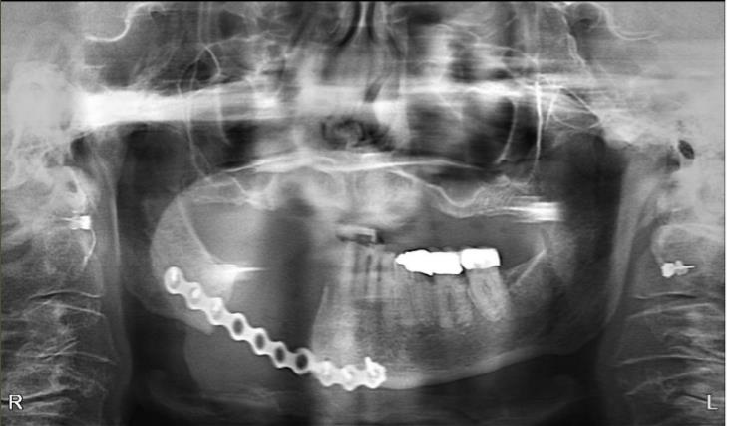

Case 1

The patient is an 80-year-old female with a history of osteoporosis for which she received Alendronate (Fosamax) 70 mg one time per week for 12 years. She stopped the medication in December 2023. She was initially seen at Denver Health in January 2024 with concerns of pain and swelling on the lower right side that had persisted for over 10 months. Her dentist had removed tooth #28 and placed an osseo-integrated implant in 2020.

The patient was noted to have extensive erosive bony changes in the right mandibular body. She was diagnosed with Stage 3 MRONJ. The mandible was resected through a submandibular approach and a reconstruction bar was placed. She is now doing well without recurrence of her MRONJ and has elected not to have definitive bony reconstruction.